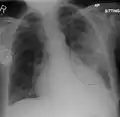

| A chest X-ray showing a very prominent wedge-shape bacterial pneumonia in the right lung | |

Normal AP CXR

Normal lateral CXR

AP CXR showing left lower lobe pneumonia associated with a small left sided pleural effusion

AP CXR showing right lower lobe pneumonia

AP CXR showing pneumonia of the lingula of the left lung

Right upper lobe pneumonia as marked by the circle.

Left upper lobe pneumonia with a small pleural effusion.

Right lower lobe pneumonia as seen on a lateral CXR